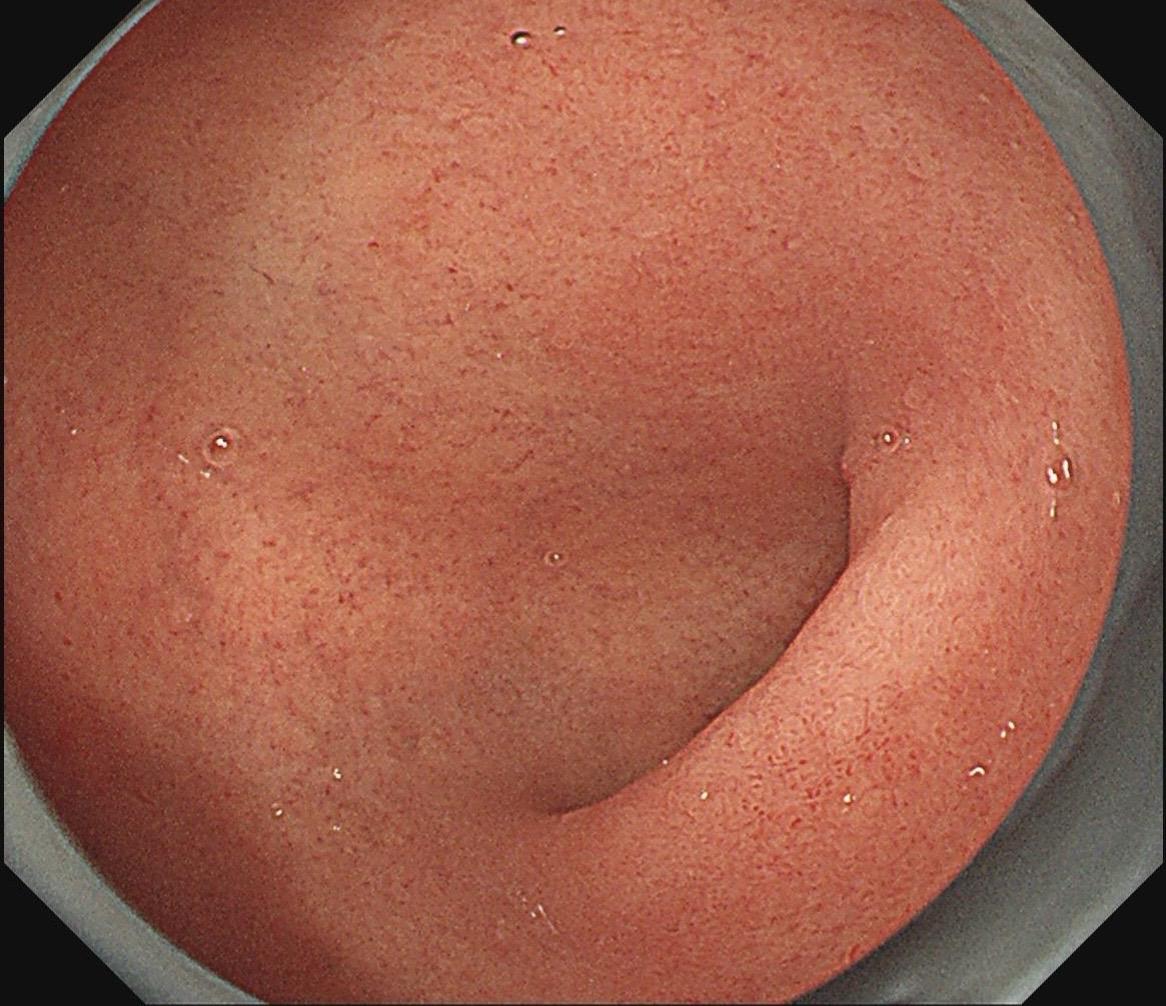

有段时间没见这么规则的网状血管了。好吧,我承认自己是个图控~